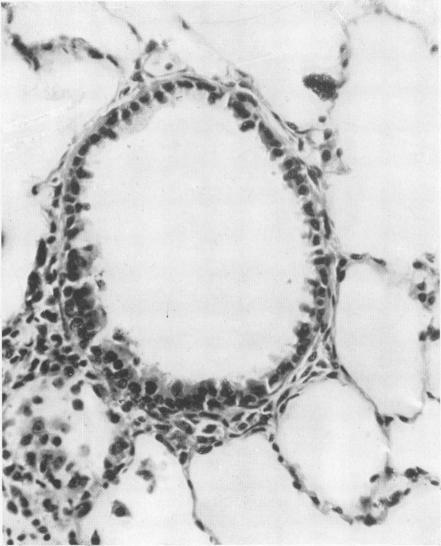

Manganese pneumonitis; further clinical and experimental observations.

Br J Ind Med. 1949 Apr;6(2):82-90. doi: 10.1136/oem.6.2.82.